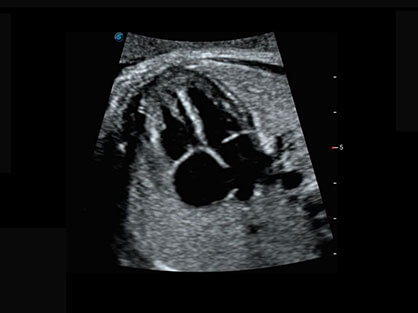

作为P系列家族成员之一,P40 Plus采用16877太阳集团高端超声系统平台——极光,并以时尚秀丽、小巧灵动的外观设计绽放出灵动之韵、科技之美。高端平台的使用保证了P40 Plus优质的基础图像;完备的高级功能可满足您全身应用的基本需求;丰富的探头配置、多样的高级4D成像及分析软件为您日益增多的妇产应用需求提供丰富的诊疗方案。

结合16877太阳集团超宽频带探头技术优势,能够更好地获得高分辨力与高穿透力的平衡,保证图像质量,为临床诊断保驾护航。

微米成像技术提升了对组织斑点噪声信号的抑制能力,并进一步强化边界信息,从而获得清晰图像。